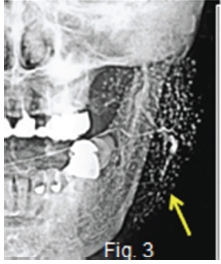

Figures 1, 2,3 & 4 refer to a syndrome reported by Sjögren in 1933, characterized by keratoconjunctivitis, dry mouth, chronic rheumatoid arthritis and swelling (green arrow) of the salivary glands. Subsequently, similar cases have been reported as Sjögren's Syndrome. The aetiology of this syndrome has remained a mystery. The syndrome occurs most commonly in middle aged women. It is a systemic disease, with the above symptoms complicated by rheumatoid arthritis, collagen disease, and autoimmune diseases, which lead to various clinical manifestations. Xerostomia is caused by hyposalivation, which may bring about arthropy, erosion, or ulcers of the oral mucosa. The cardinal sialographic findings in Sjögren's syndrome include small round shadows, called the "branchless fruit-laden tree" the appearance of which is demonstrated in Figs. 2 & 3 (yellow arrows). The degree of distension in the peripheral parts of the ducts is described as appearing in four sequential stages. Stage l is classified as the punctate pattern; Stage ll, the globular pattern; Stage lll, the cavity pattern, and Stage lV, the destructive pattern. Fig.4 is a Technetium-99 pertechnetate salivary scintigram. In contrast to strong uptake in the thyroid glands (red arrow), both submandibular and parotid glands bilaterally show minimal uptake, indicating hypofunction. In 1892, Mikulicz reported a lesion that presents as a bilateral swelling of the lacrimal glands and salivary glands. It appeared to be caused by chronic infection. Subsequently lesions with similar clinical findings have been reported, including those caused by specific inflammations, such as tuberculosis, syphilis, leukaemia and malignant lymphoma. Thus lesions resulting from any obvious cause and characterized by secondary bilateral enlargement of the major salivary glands and lacrimal glands are known are known as Mikulicz syndrome. Lesions with similar findings but of unknown origin are known as Mikulicz disease. Later, on the basis of a report by Godwin in 1962, Mikulicz disease became commonly known by the term benign lymphoeithelial lesion. The early sialographic features of this disease include irregular dilation or partial disappearance of peripheral ducts and maculation. Figure 5 is a frontal submandibular sialogram showing a distended Wharton duct (black arrow). and extensive disappearance of, or, diffuse defects of the peripheral ducts.